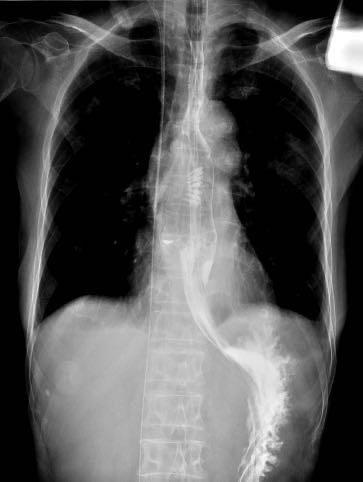

赵奶奶听了钟教授的病情解释后,恳请钟教授尽快手术。钟教授当天就安排赵奶奶住院检查,行术前评估,次日就给赵奶奶完成了内镜下微创手术:隧道内镜下食管憩室嵴切开术。钟教授运用内镜电刀在食管憩室上方建立“隧道”入口,打通“隧道”,在“隧道”内暴露出憩室嵴,最后应用内镜刀切开憩室嵴肌肉,在食管腔观察憩室嵴消失,金属夹关闭“隧道”入口。手术顺利,整个手术过程仅仅用时30分钟。术后复查造影,造影剂流出食管顺畅,不再潴留于食管憩室。赵奶奶术后经过禁食、胃肠减压、抑酸、营养支持等治疗,1天后进食流质饮食无明显不适,未再呕吐。术后逐步增加饮食,赵奶奶也未再呕吐,并且体重逐步增加,精神越来越好。就这样,困扰了赵奶奶好多年的呕吐,竟然这么快就治好了。

图1  食管巨大憩室,术前憩室嵴明显,造影剂滞留食管憩室